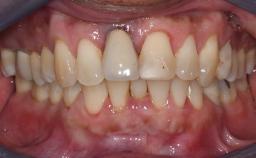

Missing Maxillary Central Incisor, Single Implant Replacement with Adjacent Tooth Restoration

The patient presented with a failing tooth-supported fixed dental prosthesis with cantilever extension replacing the right maxillary central incisor. His chief presenting complaint was poor esthetics, in particular the dark discolored margin around the abutment tooth, the maxillary left central incisor. He reported a history of trauma at a young age, which necessitated the replacement of his maxillary right central incisor as well as root canal therapy of the adjacent left central incisor. The existing prosthesis had been in situ for over 20 years. The initial periapical radiograph displayed good proximal bone levels at the adjacent teeth and a wide incisive canal, which was a concern. The left central incisor presented a very wide root canal treatment with compromised radicular dentin thickness, which was a consideration in the decision between a new tooth-supported fixed dental prosthesis vs. an implant-supported prosthesis. After a lengthy discussion on the risks and benefits of both treatment options, the patient decided on a single-tooth implant replacement.

Patient's Esthetic Expectations Low Medium High

Lip Line No exposure of papillae Exposure of papillae Full exposure of mucosa margin